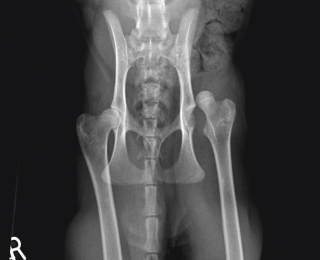

Comparison of complications and outcomes of cats with hip luxation treated with toggle rod technique using either ultrahigh-molecular-weight-polyethylene or nylon: a multi-institutional retrospective study

Coxofemoral luxation is frequently encountered in feline orthopaedic practice and is the commonest luxation in this species. A variety of surgical techniques have been described, with re-luxation rates ranging from 10-33%.1-4 Few studies have reported the use of toggle rod stabilisation for feline coxofemoral luxation.2,5,6 Very-good-to-excellent long-term outcomes were reported for 11 of 14 cats and a re-luxation rate of 14% in a study using polydioxanone.2 Excellent short-term outcomes were described for four cats using ultrahigh molecular weight polyethylene (UHMWPE).5 There are no large studies reporting use of UHMWPE or nylon for toggle rod stabilisation of hip luxation in cats, or studies that compare complications and outcomes of cats managed with UHMWPE or nylon.

The objectives of the study led by Dr Mullins are to describe the rate and type of intraoperative and postoperative complications and outcomes of toggle rod technique in cats, to compare the rate of complications and outcomes of cats treated with UHMWPE or nylon, and to identify risk factors for development of complications and non-excellent outcome. This will be a multi-institutional study involving ten referral centers. Outcome will be assessed based on the results of a designated telephone owner questionnaire.